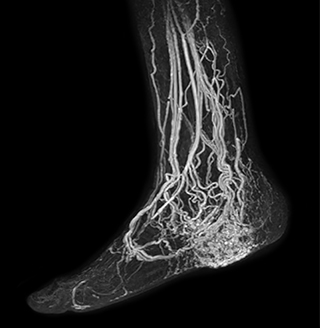

MRA of foot with 4D-TRAK XD

The images obtained with Ingenia Ambition show large coverage and high uniform signal. More vessels are visible than in a previous exam of the same patient on Achieva. The movies show a higher temporal resolution in the Ambition acquisition than in a previous Achieva 1.5T exam. Both exams use a FOV of 300 mm and voxel height and width of 0.78 mm.

Achieva 1.5T

2:30 min. TE 1 ms, TR 4 ms

Ingenia Ambition

4D Trak XD 1:54 min. TE 1ms, TR 3ms